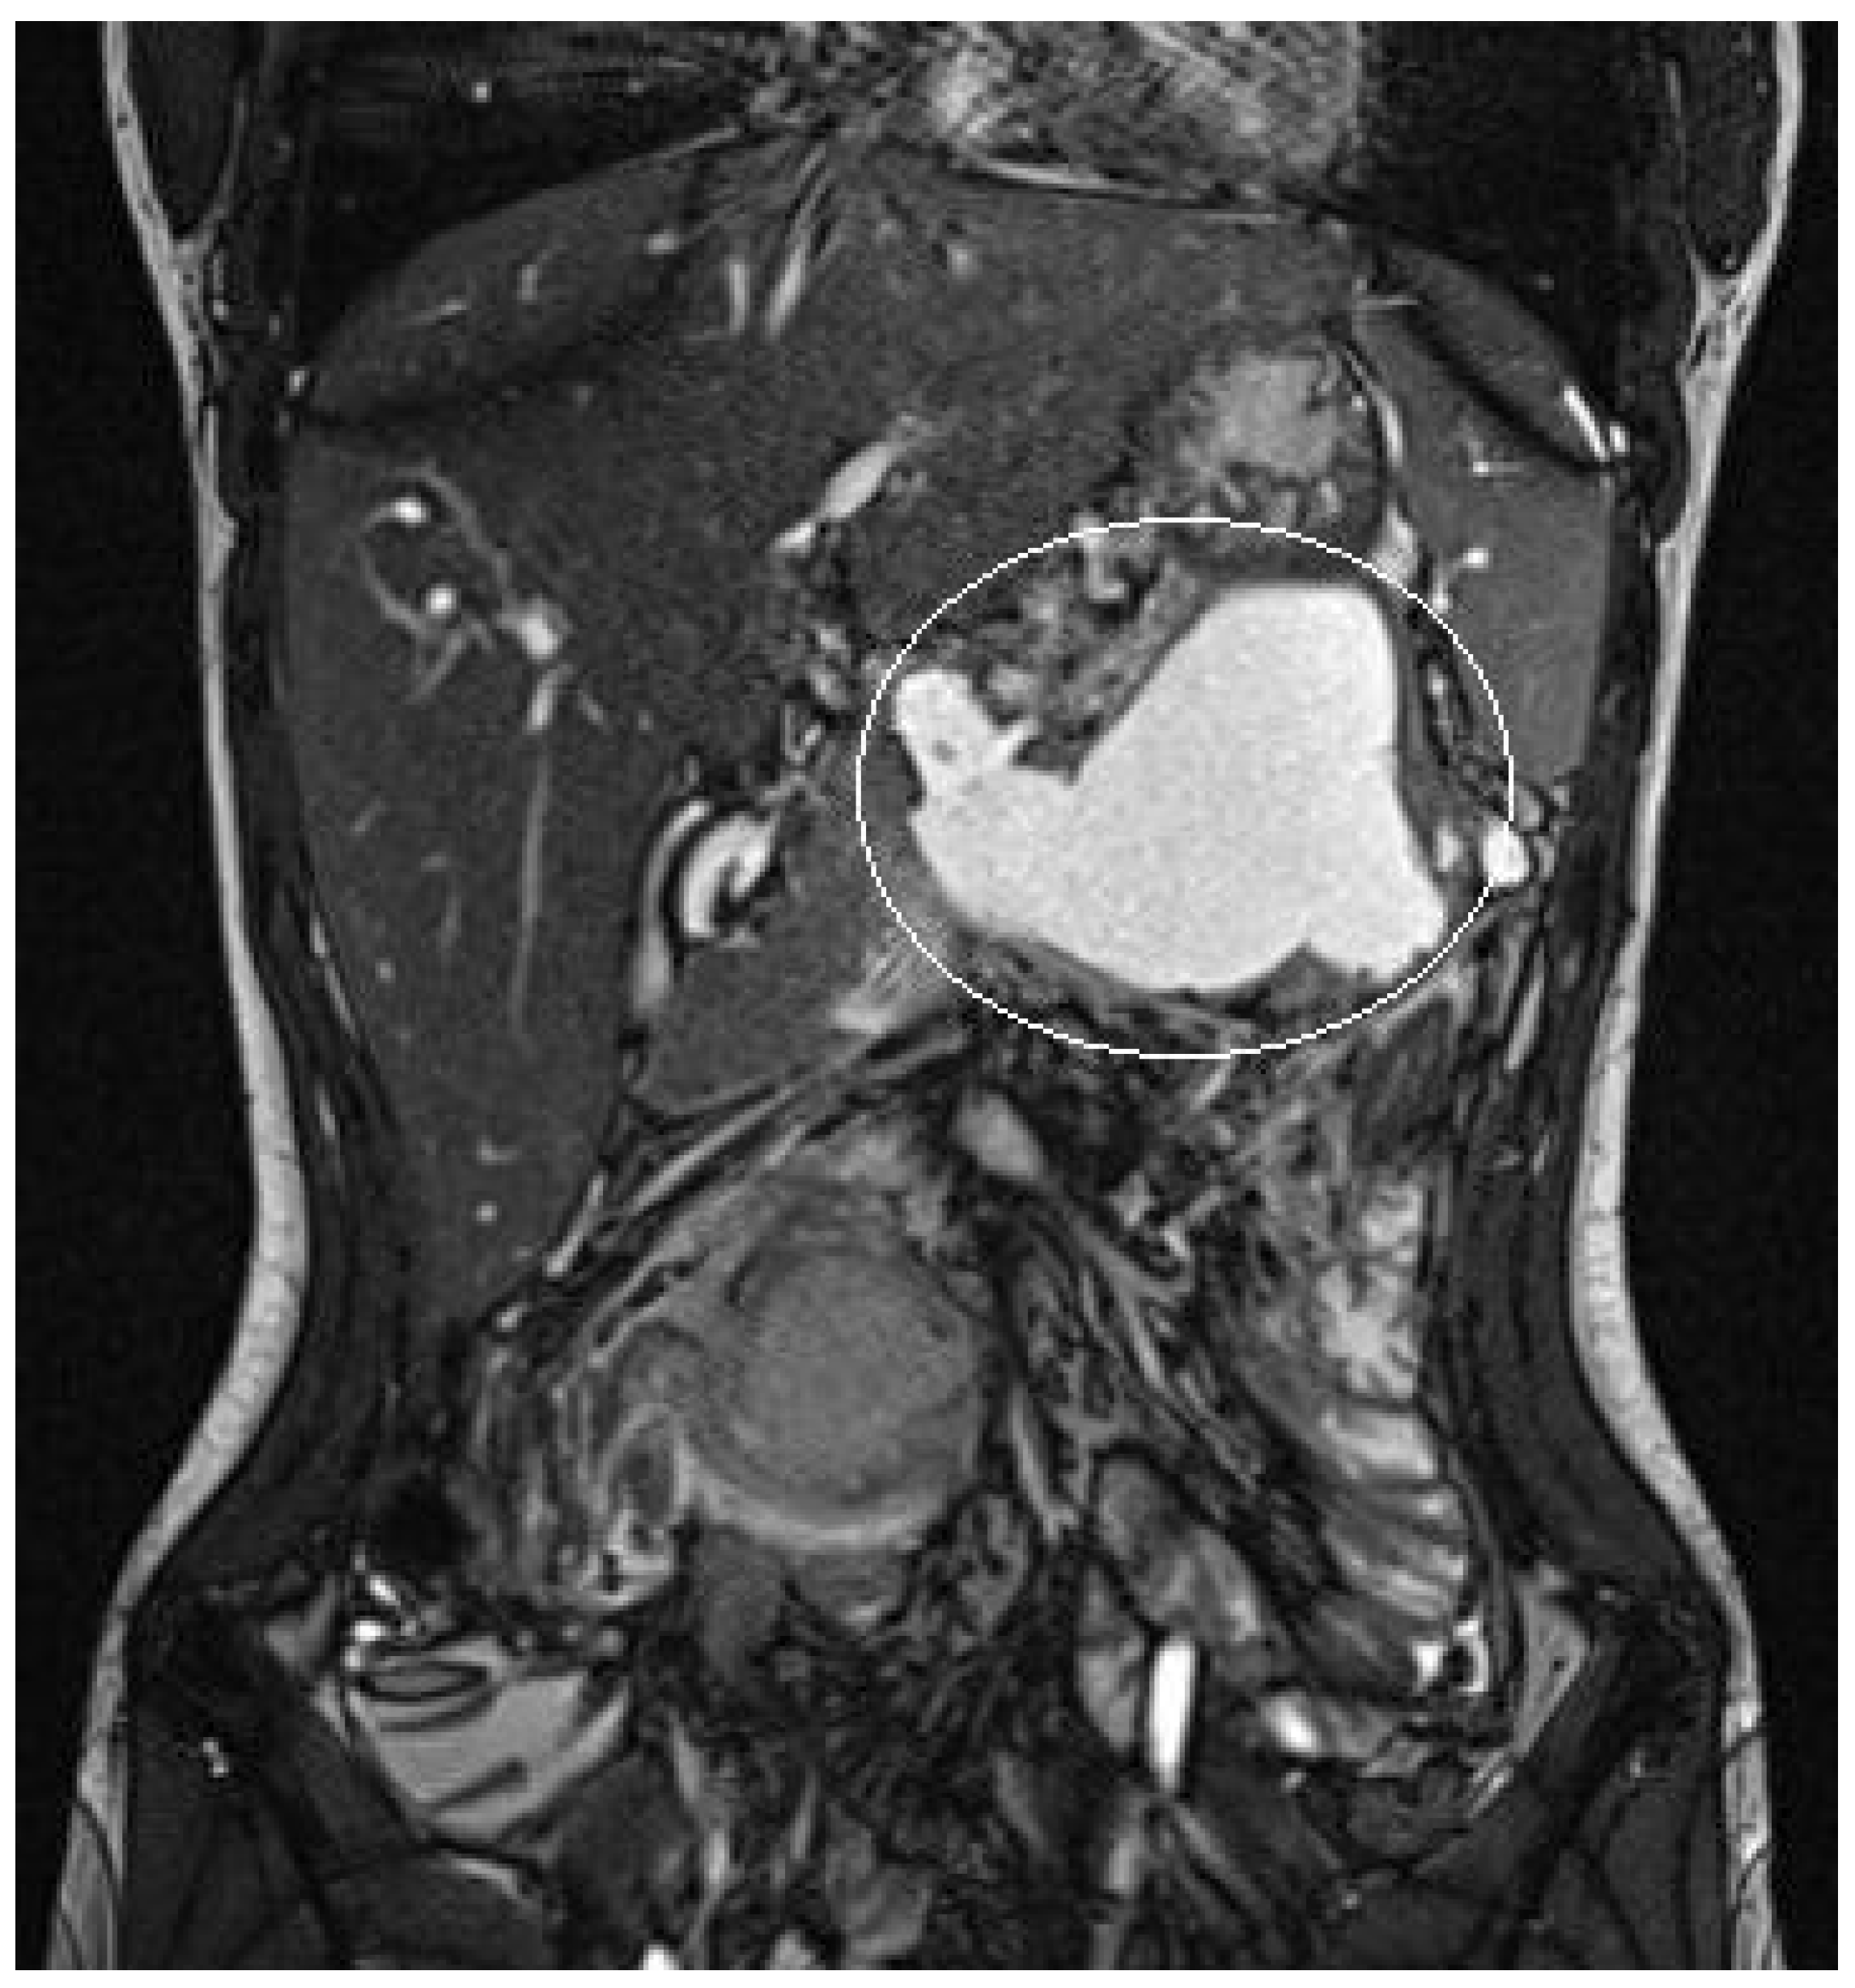

Figure 3.

Patient n°1 MRI. Pseudocyst in the omental bursa with maximum diameter 10 cm.

3.1.2. Patient n°2

A 15-year boy was affected by B-acute lymphoblastic leukemia and severe coagulopathy; he developed a chemotherapy-induced acute cholecystitis, acute pancreatitis complicated by septic shock and PFC. At MRI the major diameter of the collection was 12 cm (Figure 4). After unsuccessful attempts of conservative treatment, the boy underwent two different attempts of EUS-guided trans-gastric pseudocyst puncture and liquid aspiration, within a month between the two procedures. few days after the second one, the PFCs persisted and the boy still presented abdominal pain and fever. As the need to not delay chemotherapy was pressing, the patient underwent EUS-guided cystogastrostomy and EC-LAMS positioning as a rescue procedure. Post-operative course was uneventful. MRI performed 14 days after the procedure showed a significant reduction of the pseudocyst, which was no longer visible on the ultrasound performed right before its removal. EC-LAMS stayed in place for a total of 28 days and was endoscopically removed, without any intra-operative or post-operative complication.

Figure 4.

Patient n°2 MRI. Pseudocyst with maximum diameter 12 cm in the left hypochondrium in close proximity to the posterolateral wall of the stomach.